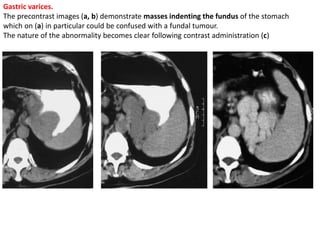

Gastric varices.

The precontrast images (a, b) demonstrate masses indenting the fundus of the stomach

which on (a) in particular could be confused with a fundal tumour.

The nature of the abnormality becomes clear following contrast administration (c)